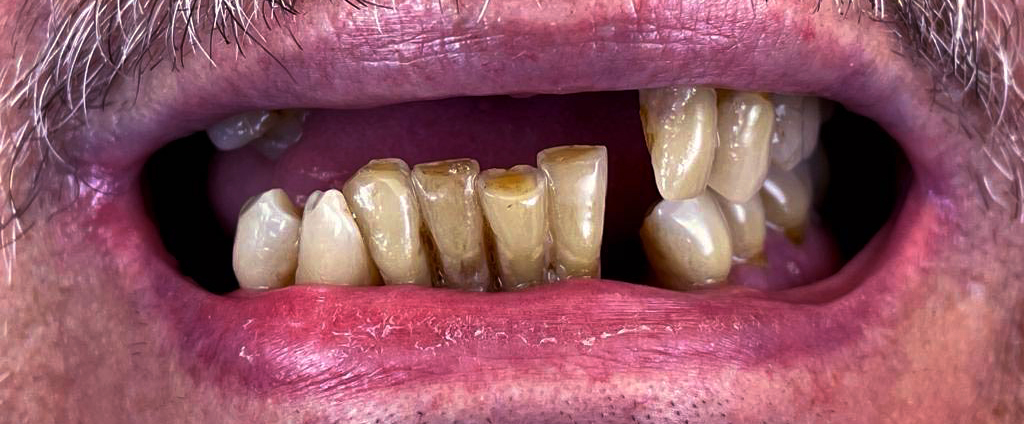

1. Konsultacja z ekspertem

Podczas pierwszej wizyty lekarz implantolog wykonuje badanie wewnątrzustne, tomografię komputerową (CBCT) podczas której, weryfikuje ilość oraz jakość kości wyrostka zębodołowego. Jeśli z powodu znacznej atrofii wykonanie metody All-on-6 okaże się niemożliwe zaproponujemy inne rozwiązanie. Konsultacja taka kończy się wykonaniem planu leczenia wraz z kosztorysem.

Na tym etapie rozpoczynamy proces planowania leczenia. Spotkasz się z lekarzem implantologiem oraz zostanie przeprowadzona pełna higienizacja Twoich zębów. Ponad to, pobierzemy cyfrowy wycisk jamy ustnej, wykonamy niezbędne fotografie oraz wykonamy pełną diagnostykę w celu przygotowania szablonów chirurgicznych i prac tymczasowych.